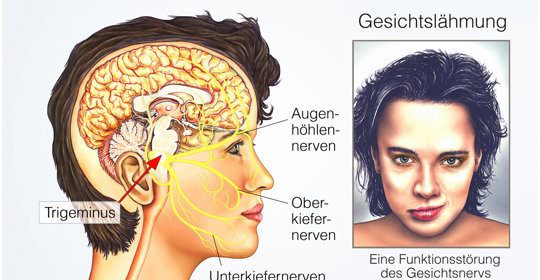

神經麻痺困擾中:瞭解成因與有效康復策略!

交感神經亢進:身體的過度緊張,症狀分析與科學調理方法